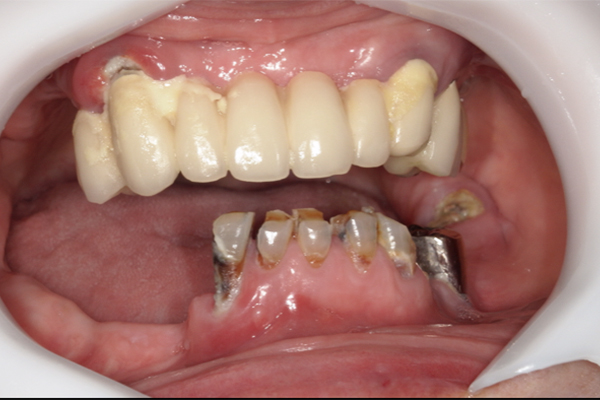

| 主訴 | 全体的にきれいにしたい |

| 治療内容 | 午前中に上下顎共に重度の歯周病、虫歯のため全ての歯を抜歯させていただき下顎はインプラントの土台を3本埋入し歯型を取り午後に上部構造(下顎全ての歯)を装着、上顎は一度総入れ歯を装着させていただきました。 治療が1日で完了しその日のうちに噛めるようになります。 |

| 治療期間 | 2回(1回目に資料取りをさせていただき2回目に下記の全ての治療をさせていただきました。) |

| 治療費 | 250万円 |

| 治療 リスク | 抜歯した部位などに関しては当日痛みが出ますので痛み止めなどを処方させていただきます |